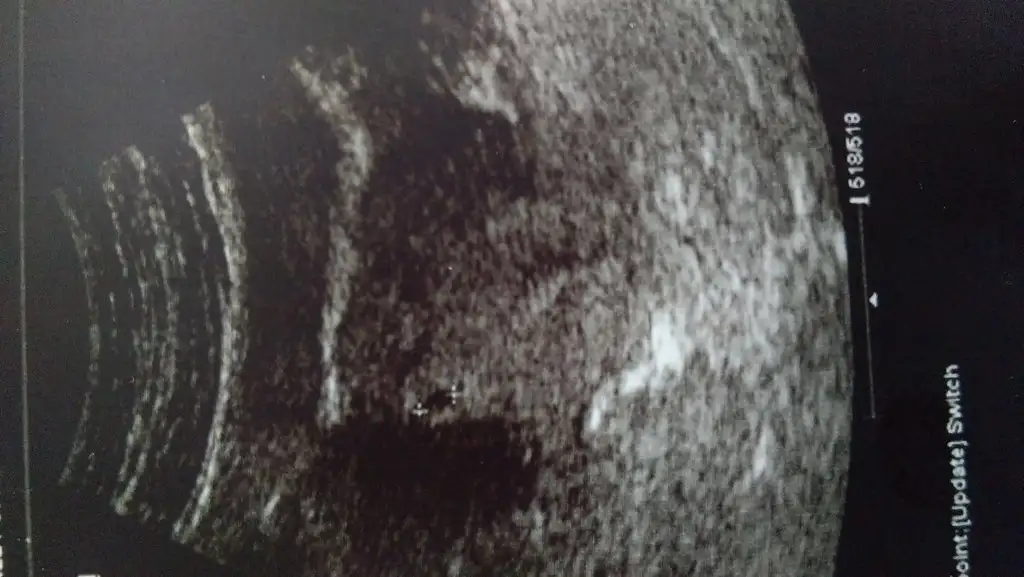

Hellööö kızlar selam. 2 tane bebişimi 8 haftalıkken kalbi atmadığı için kaybettim. 2 tane de kimyasal gebeliğim var. Vee şimdi gene hamileyim. 5+2 kese 5.3mm doktor haftasıyla uyumlu dedi. Hamilelerin duası kabul olur derler bu sefer sağlıkla doğması için bana da dua edermisiniz? :))